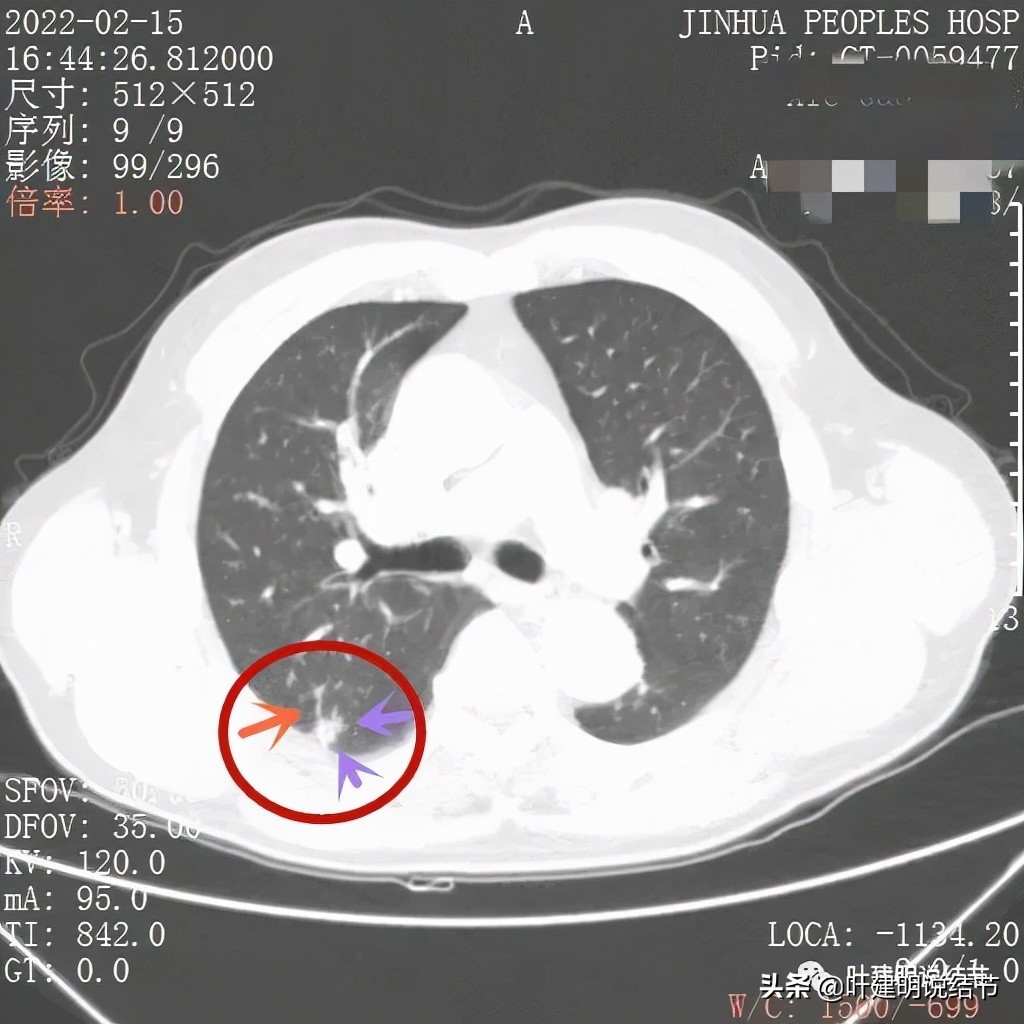

我们再来看薄层的CT图像:

病灶出现,虽然此层面还很小,但也是实性的,有微血管进入(桔色箭头)

上图更清楚显示血管进入病灶,病灶与胸膜间点状相接,感觉病灶有膨胀性,圆形或类圆形的

病赤边缘不平整,感觉毛糙(紫色箭头),此层也见血管征(桔色箭头)